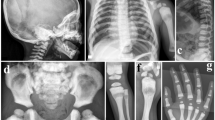

A novel 27-bp duplication in exon 1 (78dup27) in TNFRSF11A was found in four affected individuals and one asymptomatic individual. Although this duplication was the same length as the previously identified mutation (27 bp, from bases 78 to 104), in our patients the nine duplicated amino acids in the RANK signal peptide were LLLLCALLA. The phenotypes of affected individuals in this family overlapped with both early onset PDB and classic PDB, but several distinguishing features were found in our patients. The key difference between our familial PDB and the Japanese early onset PDB was the age of onset, which in most of our patients was during their late 20s (except for the propositus' niece). Another notable difference was that the propositus' son (24 years old), who carried the 78dup27 mutation, had no clinical symptoms or bone abnormalities, except for increased serum ALP, OC and CTX.